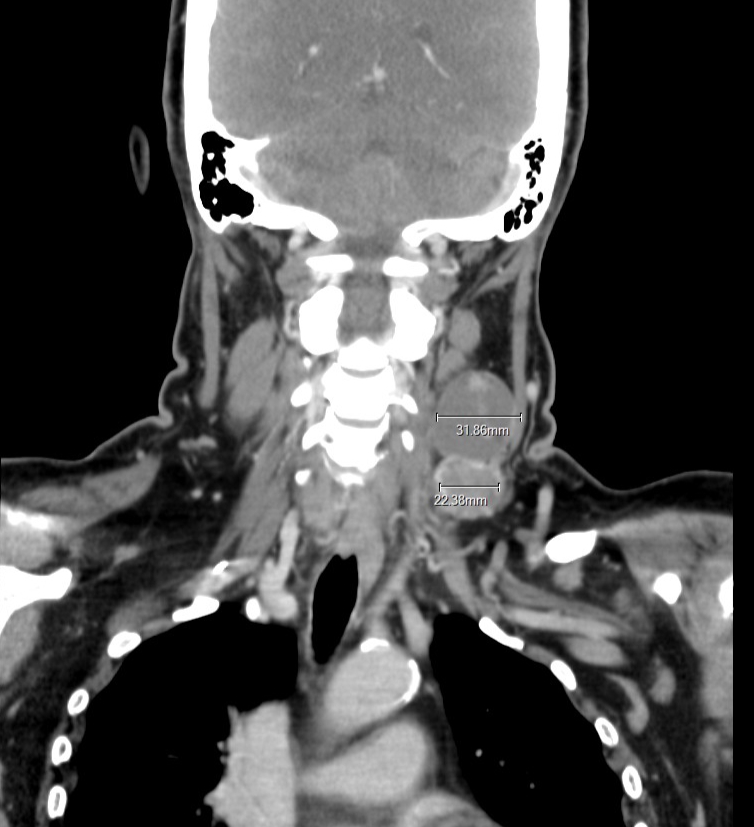

คุณแม่เป็นมะเร็งไทรอยด์ (papillary Thyroid Carcinoma) ระยะที่ 3-4 คือลามไปต่อมน้ำเหลืองแล้ว ต่อมน้ำเหลืองขนาด4-5 เซน ประมาณไข่ไก่เบอร์0 คุณหมอบอกแบบนั้น ตอนนี้แม่กับเราเดินมาถึงปลายอุโมงค์แล้ว คือการรอผ่าตัด